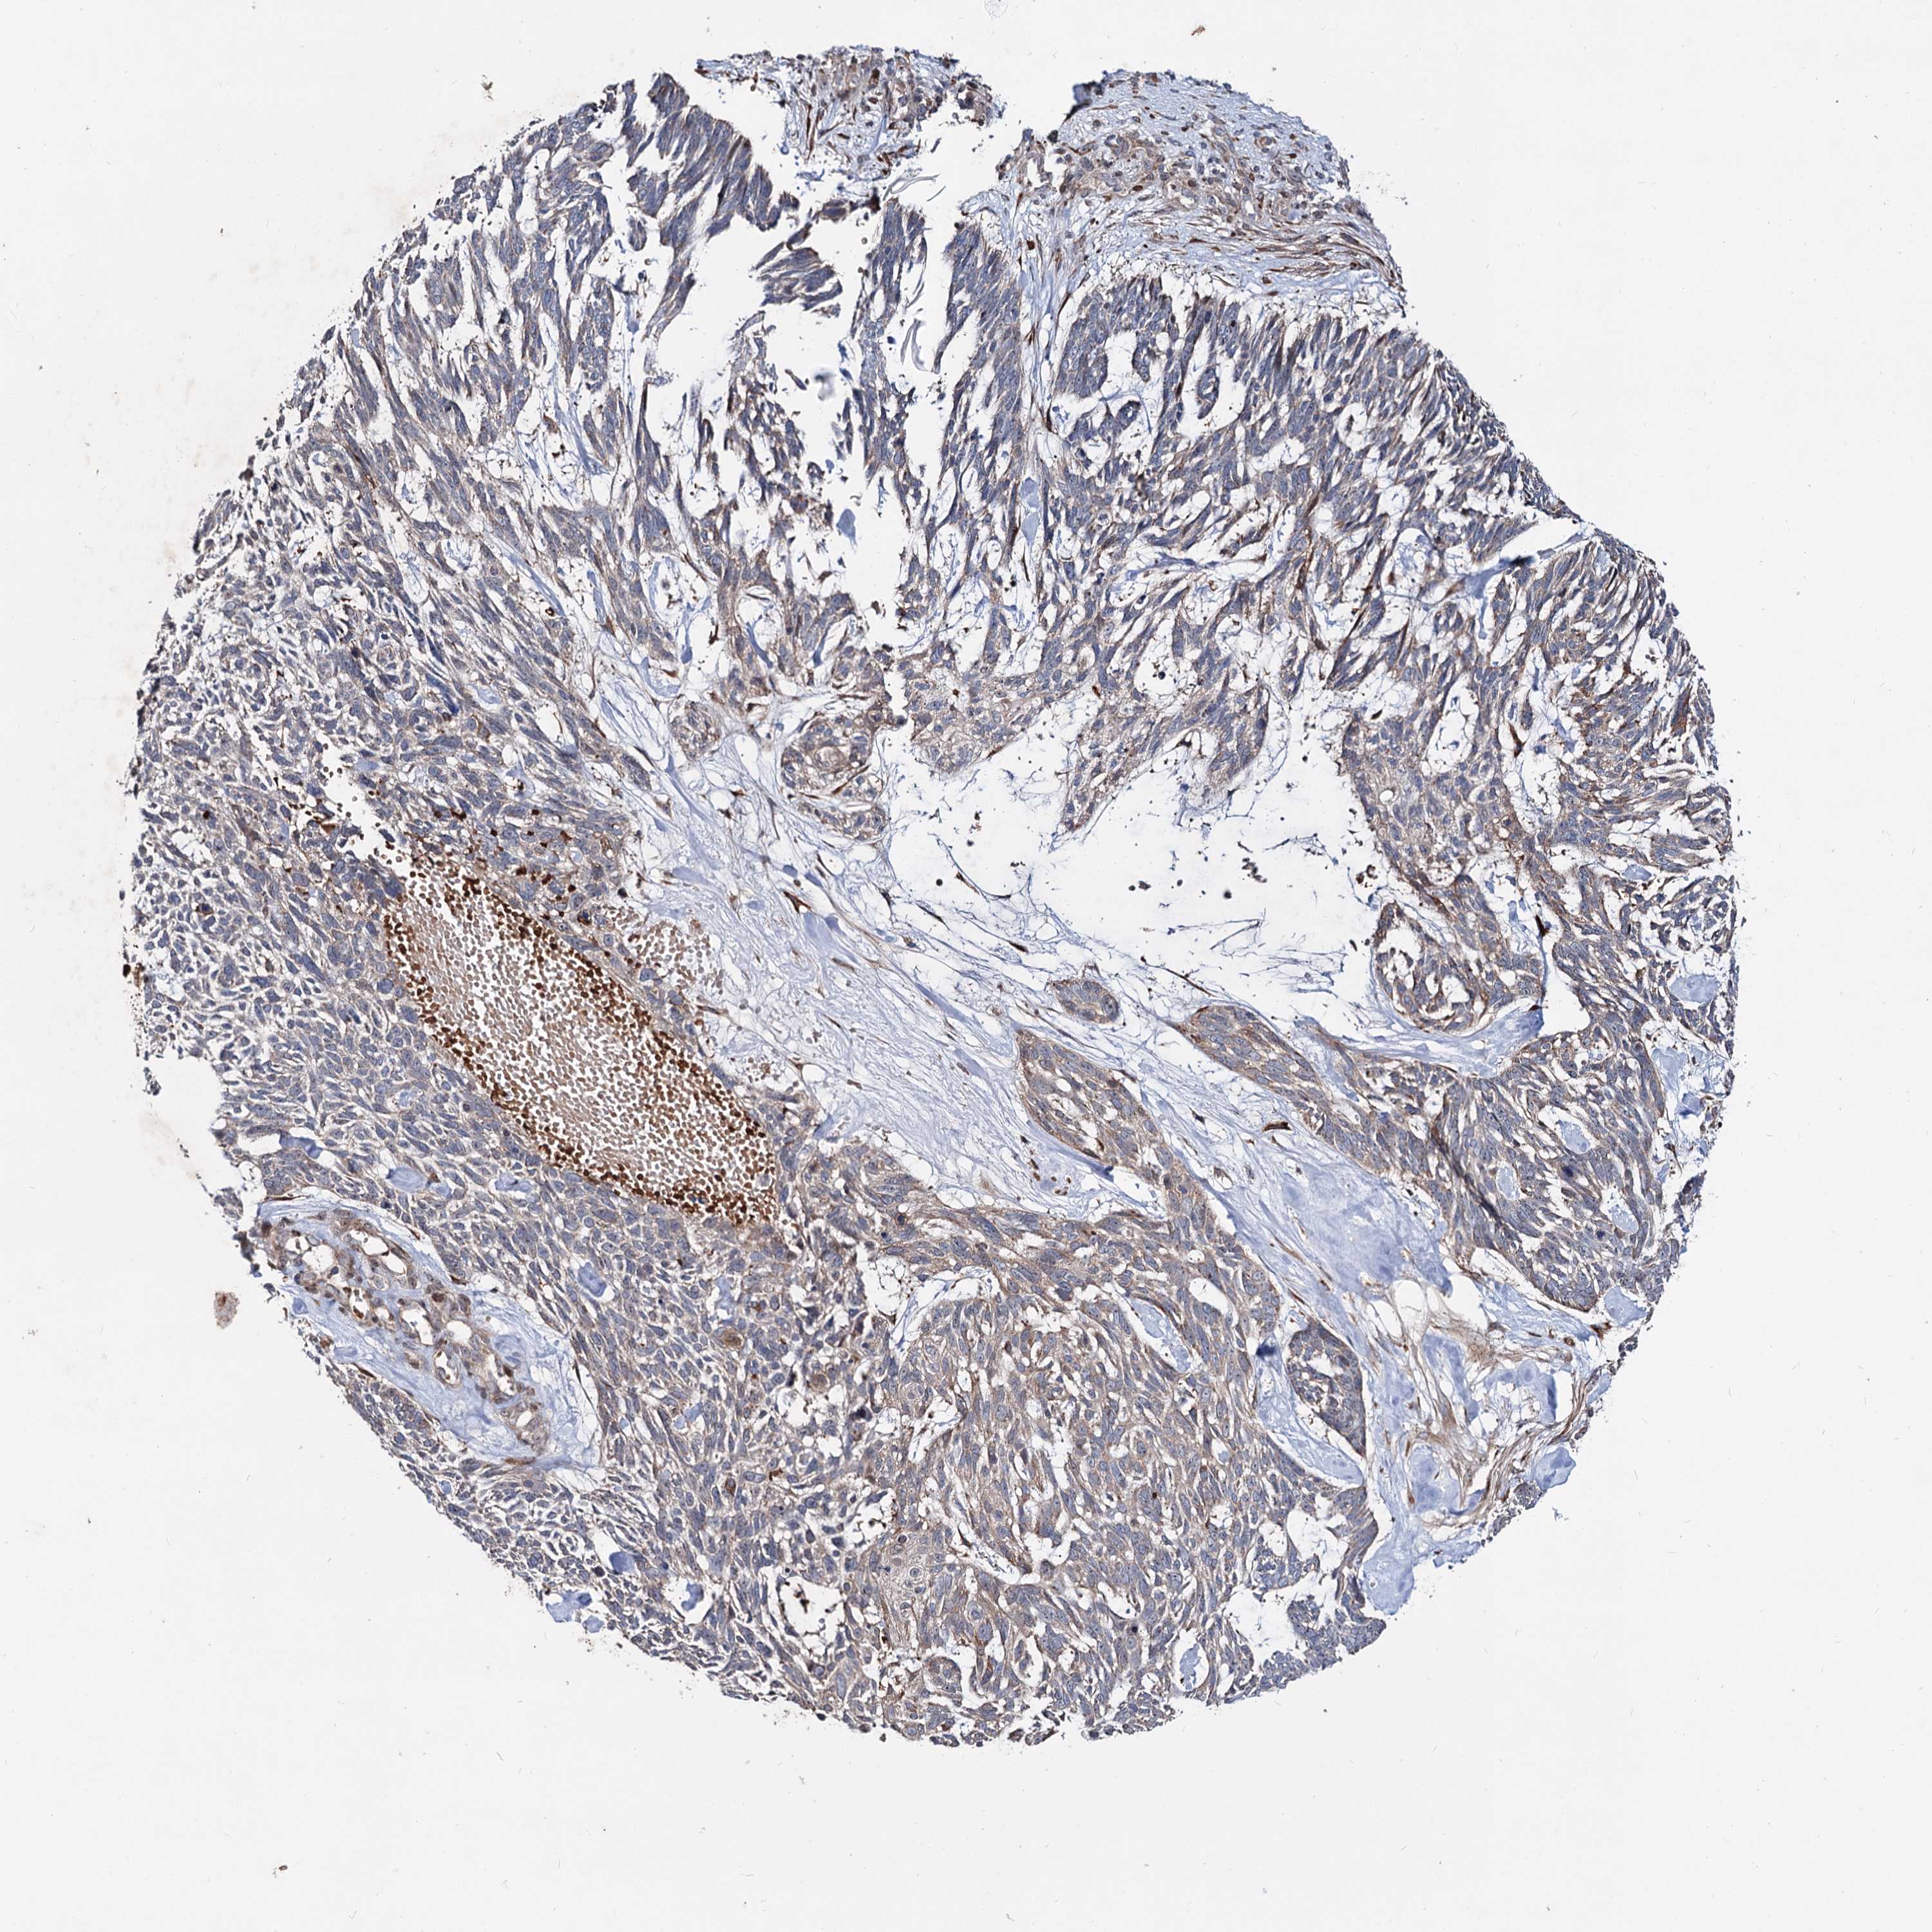

Basal cell and squamous cell cancer

SKIN CANCER - Protein expressioni

A mouse-over function shows sample information and annotation data. Click on an image to view it in a full screen mode. Samples can be filtered based on level of antibody staining by selecting one or several of the following categories: high, medium, low and not detected. The assay and annotation is described here.

Each image is clickable and will lead to virtual microscopy that enables deeper exploration of all samples and also displays staining intensity scores, fraction scores and subcellular localization as well as patient and tissue information for each sample.

Antibody HPA038929

Squamous cell carcinoma, metastatic, NOS

Squamous cell carcinoma, NOS